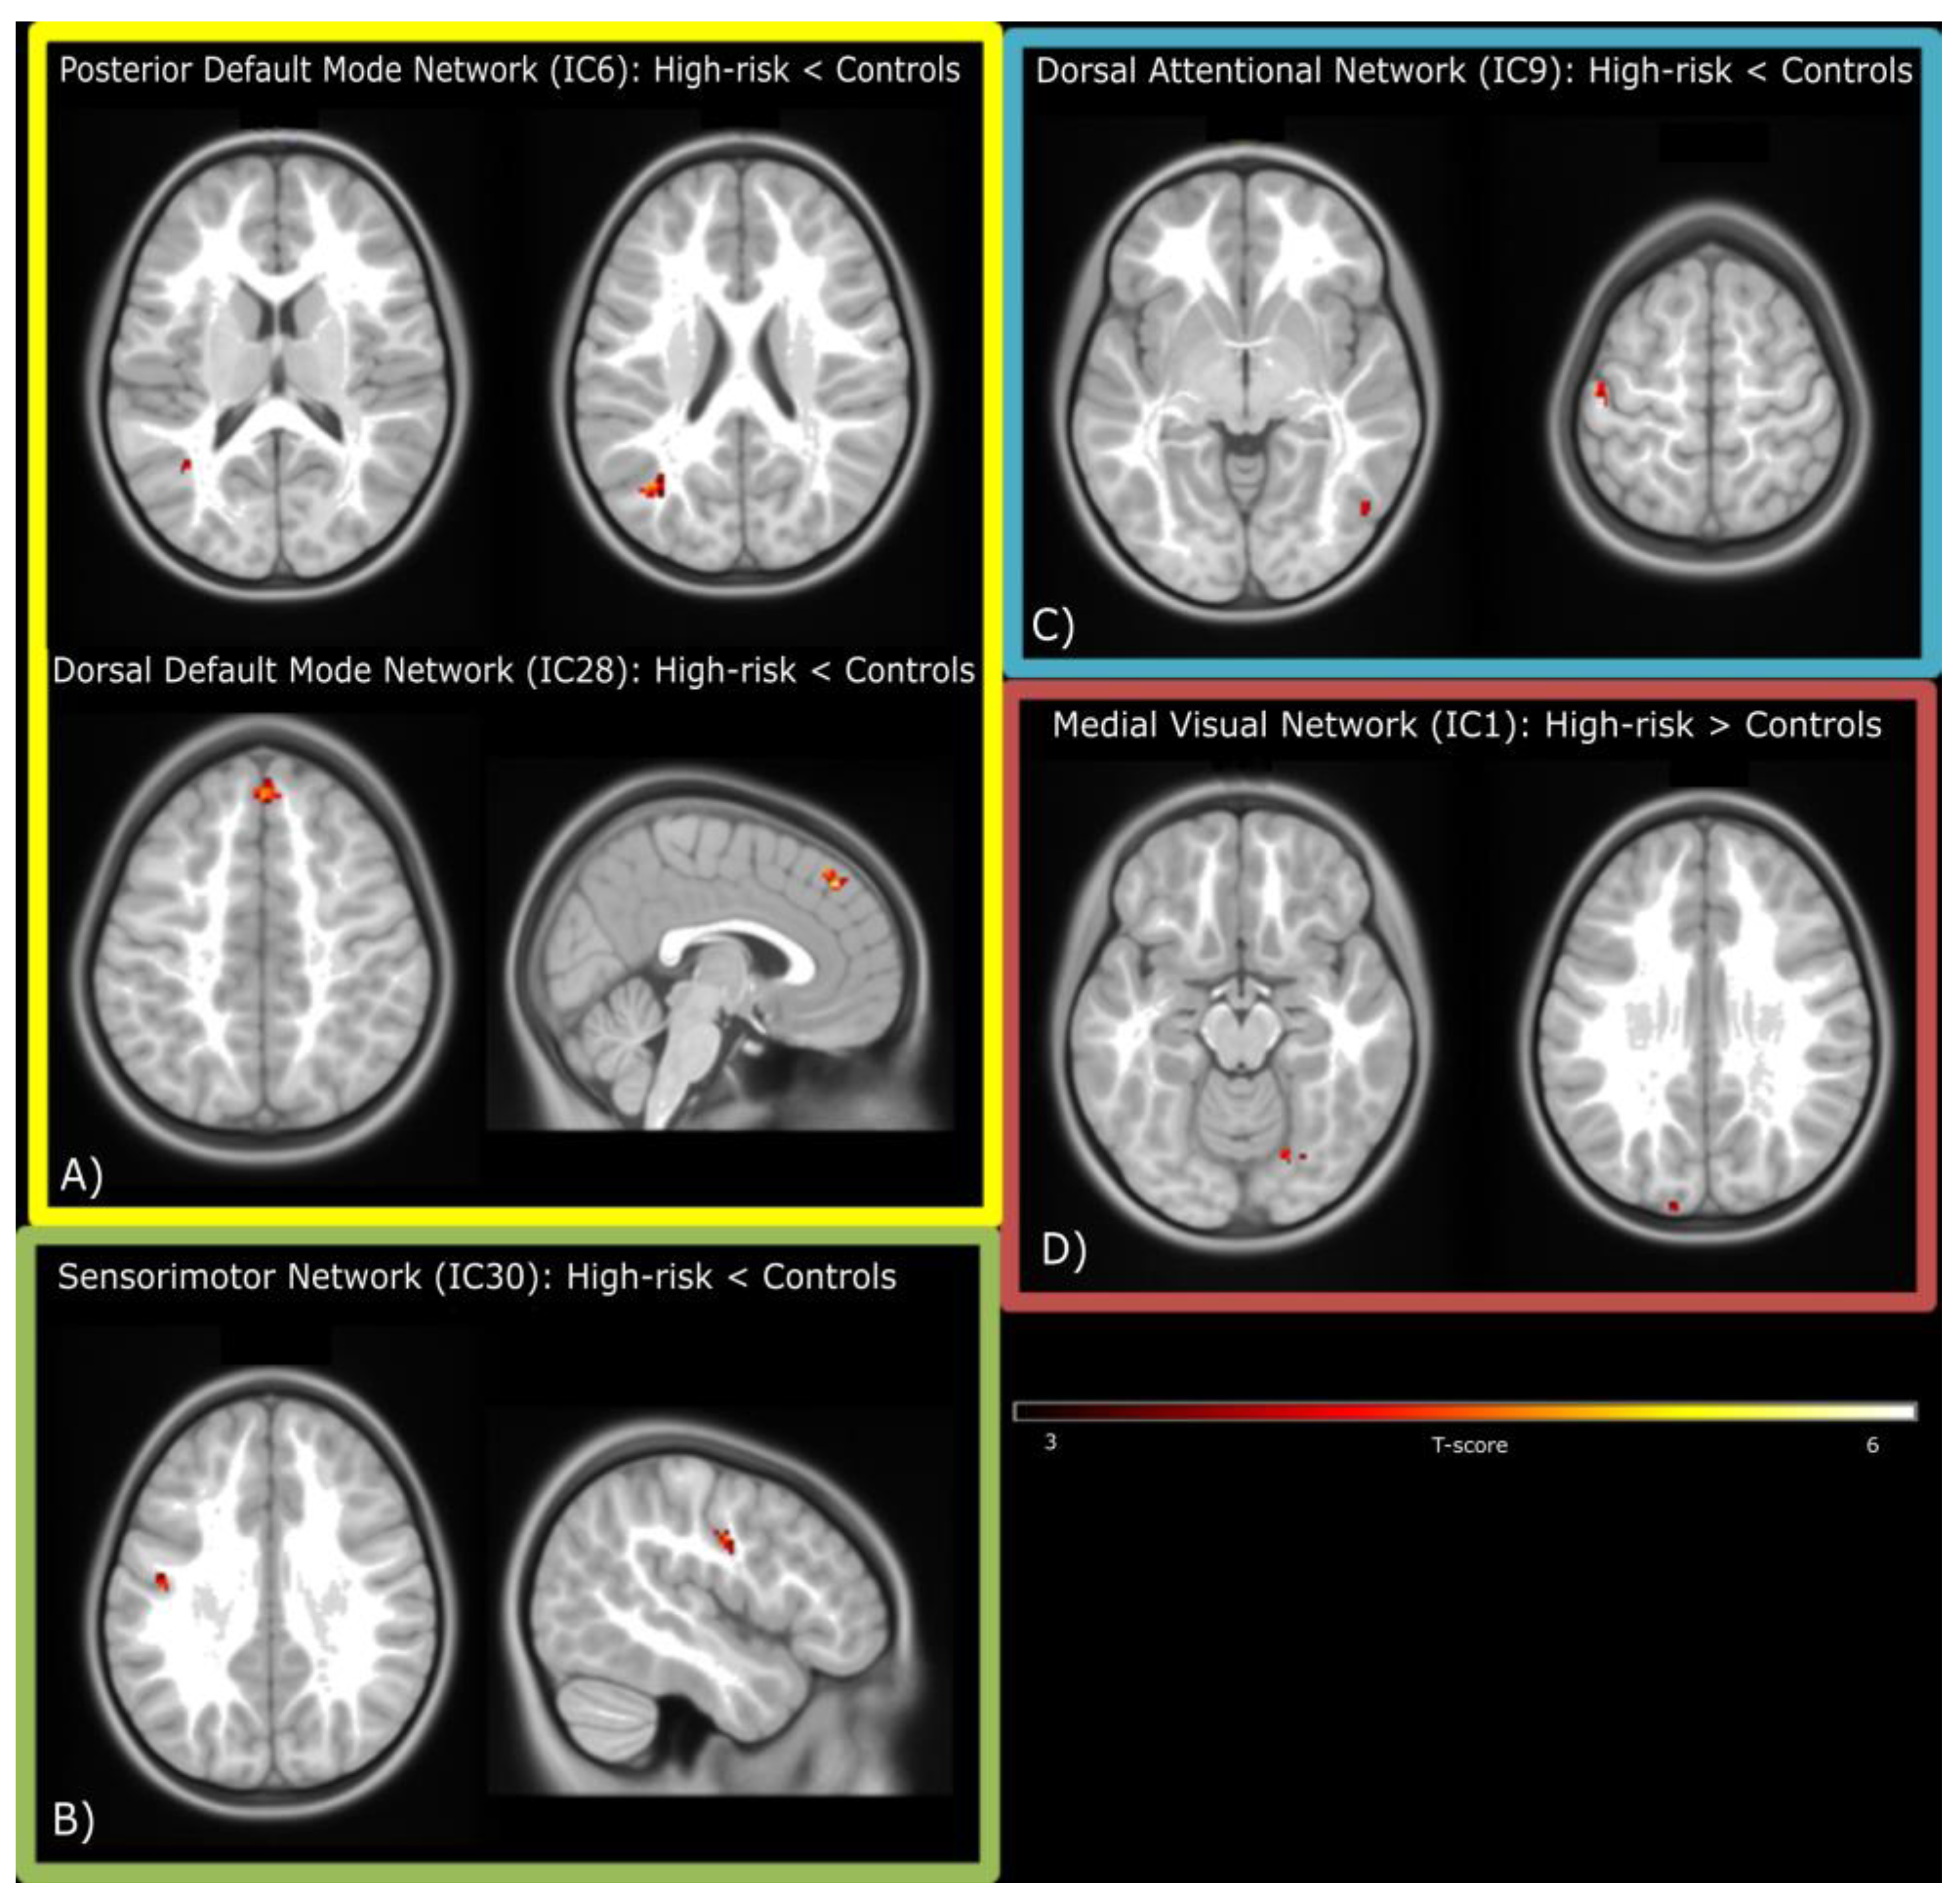

| Regions | Hemisphere | T | n Voxels | p-Value (FDR Corrected) | x | y | z |

|---|---|---|---|---|---|---|---|

| Posterior DMN (IC6): Controls > High-risk ED children | |||||||

| Angular Gyrus | Left | 4.99 | 22 | 0.048 | −38 | −66 | 22 |

| Middle Temporal Gyrus | Left | 4.61 | 31 | 0.016 | −40 | −60 | 12 |

| Dorsal DMN (IC28): Controls > High-risk ED children | |||||||

| Medial Superior Frontal Gyrus | Right | 5.8 | 52 | <0.001 | 2 | 42 | 44 |

| Sensorimotor Network (IC30): Controls > High-risk ED children | |||||||

| Postcentral Gyrus | Left | 4.7 | 25 | 0.012 | −46 | −10 | 34 |

| Attentional Network (IC9): Controls > High-risk ED children | |||||||

| Postcentral Gyrus | Left | 5.78 | 32 | 0.03 | −48 | −18 | 62 |

| Inferior Temporal Gyrus | Right | 5.22 | 24 | 0.03 | 50 | −64 | −2 |

| Visual Network (IC1): High-risk ED children > Controls | |||||||

| Fusiform Gyrus | Right | 4.79 | 21 | 0.028 | 22 | −64 | −12 |

| Superior Occipital Gyrus | Left | 4.6 | 29 | 0.024 | −14 | −100 | 26 |